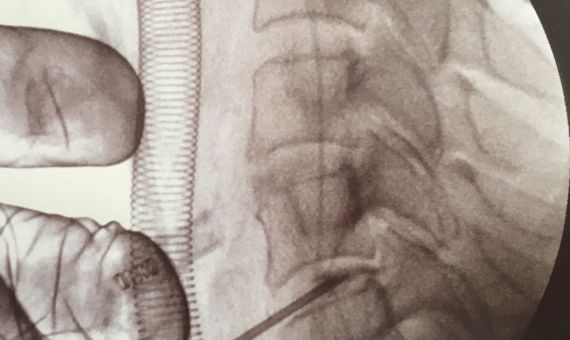

Imagen de la triple hernia cervical

Mediante este pequeño corte en la piel y un endoscopio de menos de 5 milímetros de diámetro se pueden visualizar todas las estructuras de la columna cervical y abordar de forma segura la hernia discal. La visualización de todas las estructuras anatómicas de la columna, a través de una cámara de alta definición e irrigación continua, facilita al cirujano un trabajo seguro y preciso en la columna cervical.

El Morgenstern Institute of Spine fue pionero en practicar este tipo de intervenciones en la lumbar con excelentes resultados y ahora la ha aplicado con éxito en la columna cervical para tratar una triple hernia discal cervical.